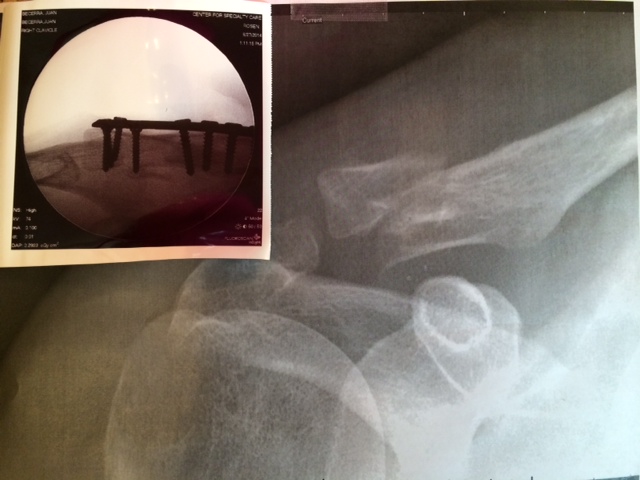

They told us to get there at 9:30 am, they took us in at 10:00 by 10:40 they put him in the stretcher, there was still someone ahead… I heard nothing until 1:30 pm, when the doctor came out with these pictures and made me a little drawing to explain how loose and up and twisted the little loose piece was. Surgery took two hours. He said it was quite probable not going to heal well if we didn’t have the surgery as the loose bit of bone was quite twisted and out of place. One more hour till he’d wake up.

Seven screws!! Apparently, it was tough to get it all in place!!! now he has a huuuuuge bumpy bandage thing on the shoulder (I was barely able to put his shirt on one side to get him in a cab!!) and MORE MORE pain. When he woke up he told the nurse to shut up and get him food, hahahahahaaaaaa! crazy man.